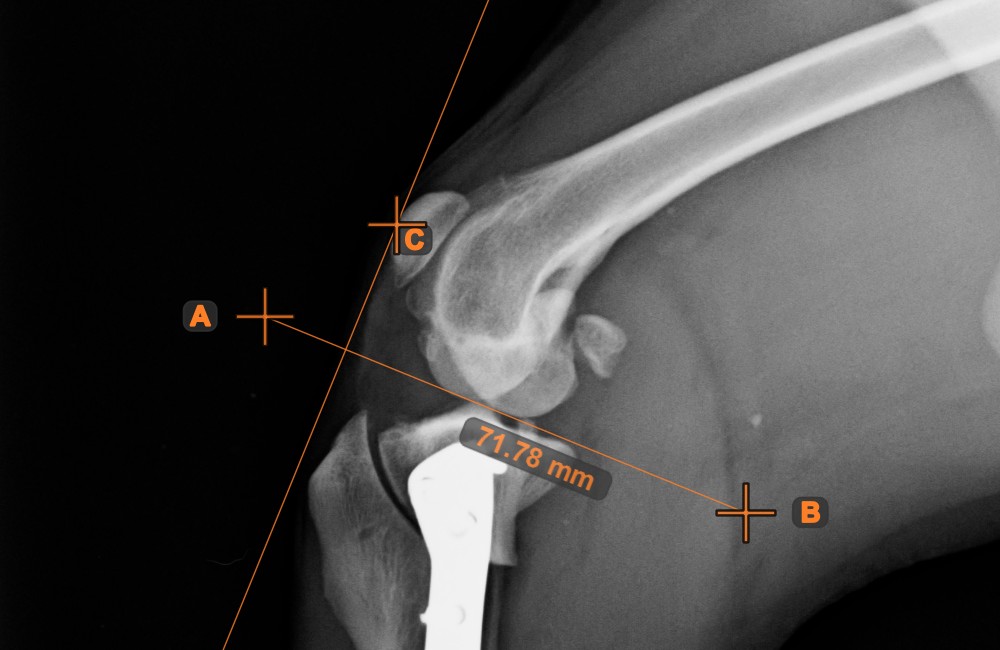

Create a line measurement to calculate the distance between two points with high precision.

Select the Line Measurement tool and assign it to one of the available mouse buttons. Place the start and end points on the scene or select them from already existing points on the image. The distance between the two points will be automatically calculated by using the default calibration data, or the recalibrated data by the length calibration measurement.

Modify the start and end point by using the Select/Move Item tool. The distance between the two points will be automatically recalculated.